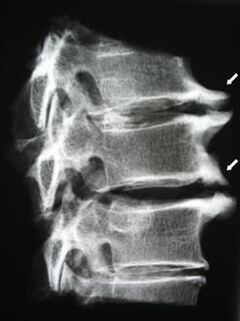

Boshlang'ich bosqichda osteoxondroz MRi-dan foydalanib aniqlandi. Keyinchalik patologiya rentgenografiyasidan foydalanishda tashxis qo'yish mumkin. Bachadon bo'yni rentgenografiya rentgenogrammalarida umurtqalar orasidagi masofa va qirrali bo'g'inlardagi masofa kamayishi va osteofitoz sezilarli bo'ladi.